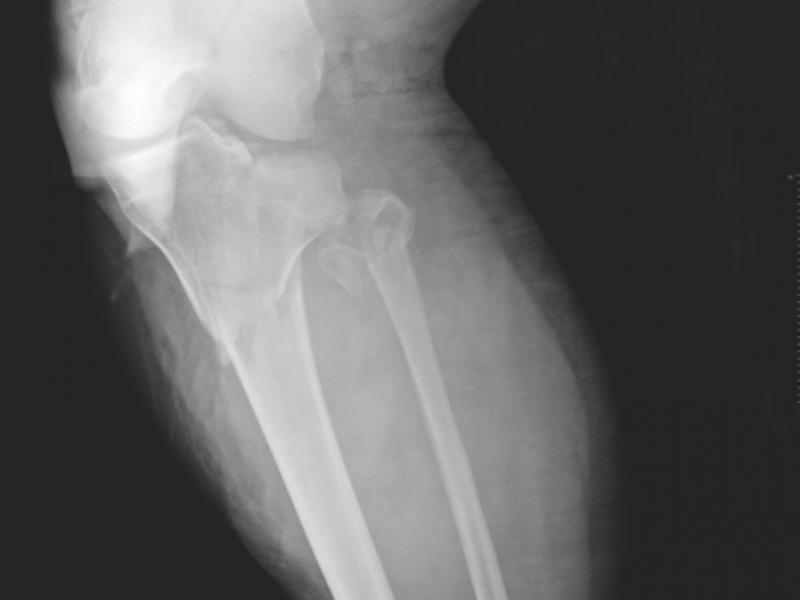

A 25 yo male presents with severe left leg pain after